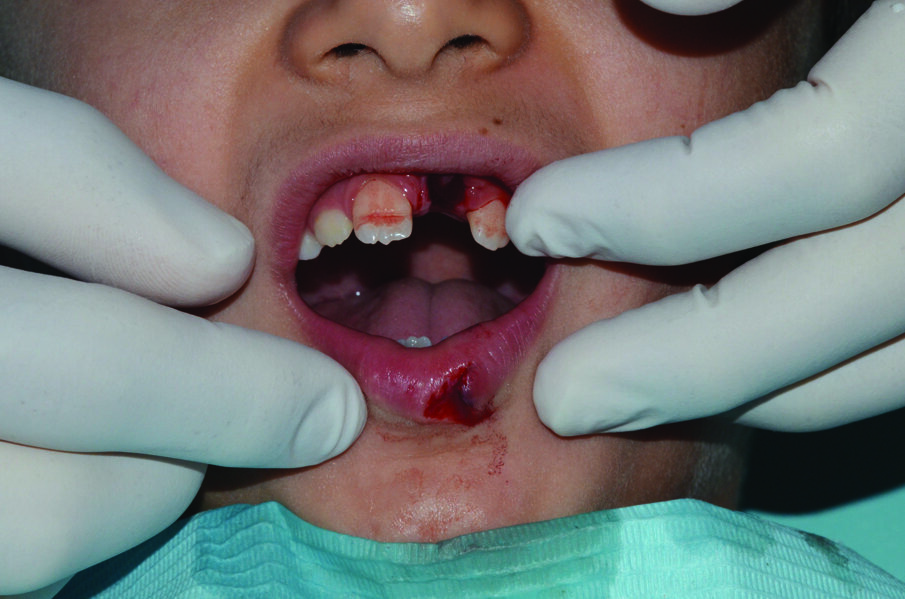

An 8-year old child presented to the department of paediatric dentistry at the Hamdan Bin Mohammed College of Dental Medicine (HBMCDM) at the Mohammed Bin Rashid University (MBRU) in Dubai Healthcare City. He allegedly fell off a climbing wall, and knocked out his upper left maxillary incisor (tooth # 21) and cut his lower lip (Figures 1 and 2). This occurred at 14:15 hours at school, and the school nurse called the patient’s mother at 14:20 hours. The patient’s mother asked the nurse to find the tooth and put it in milk. The tooth’s “dry time” was thus around 10 minutes. The patient attended with both his mother and aunt, to our specialist clinic at 14:55 hours.

• Lower lip through- and-through ragged laceration of the lower lip (Figure 1).

Figure 1: Initial presentation. 21 was avulsed and its socket appeared empty. There was a laceration of the lower lip